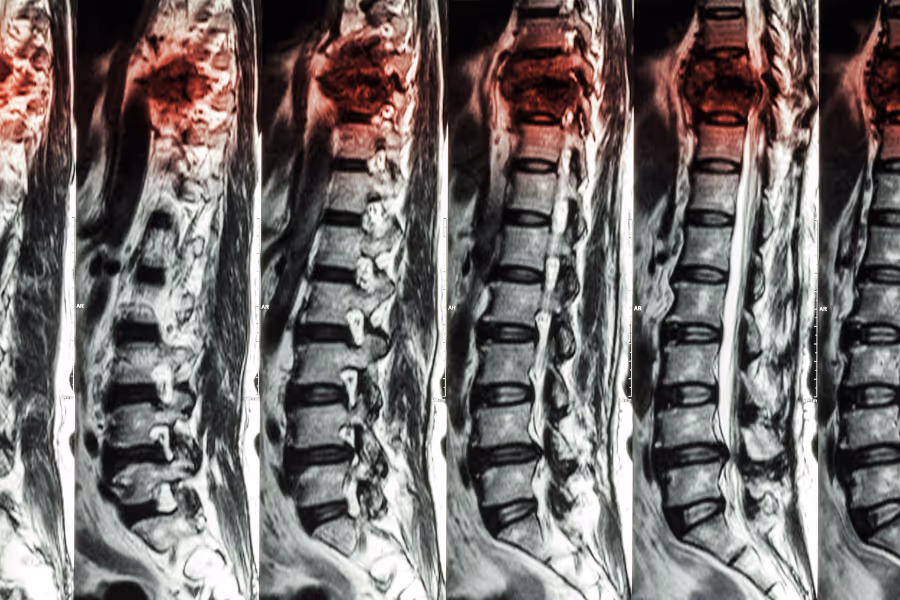

Kyphoplasty is a minimally invasive spine procedure used to treat painful compression fractures in the vertebrae (the building blocks of your spine). Imagine one of those blocks gets crushed down, often from osteoporosis or a hard fall. That collapse can cause sharp back pain and change your posture.

During kyphoplasty, the surgeon uses live X‑ray to guide a needle into the broken vertebra through a tiny skin puncture. Through this needle, a small balloon is slid into the bone and gently inflated. This can help lift the collapsed area and create a controlled space inside the vertebra. Once the space is shaped, the balloon is removed and the cavity is filled with a special bone cement. The cement hardens quickly, stabilizing the fracture from the inside so the bone doesn’t keep shifting.

Kyphoplasty doesn’t replace the whole vertebra; it reinforces the damaged part. The goal is simple: stabilize the crushed bone so movement hurts less, standing and walking feel more secure, and you can get back to everyday activities with better comfort.